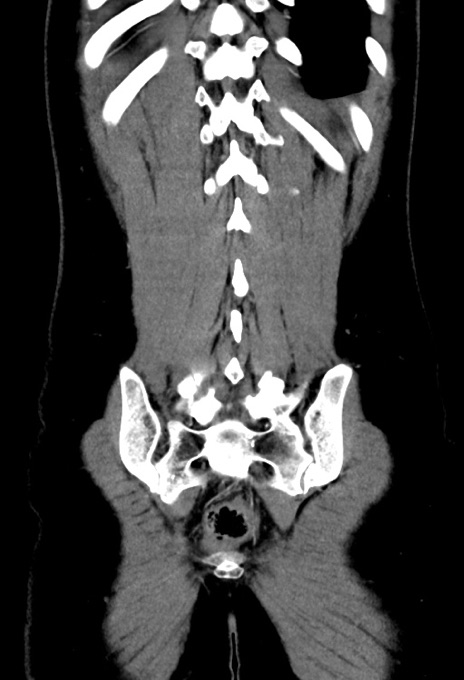

症例17(冠状断像)

【症例】20歳代女性

【主訴】嘔吐、下腹部痛

【現病歴】昨日夕食後に嘔吐し下腹部痛が出現。本日になっても嘔吐持続し改善しないため来院。

【身体所見】意識清明、BT 37.2℃、BP 108/67mmHg、腹部:平坦、やや硬、下腹部正中から右にかけて圧痛あり、反跳痛軽度あり、tapping pain(+)。

【データ】WBC 13600、CRP 14.94